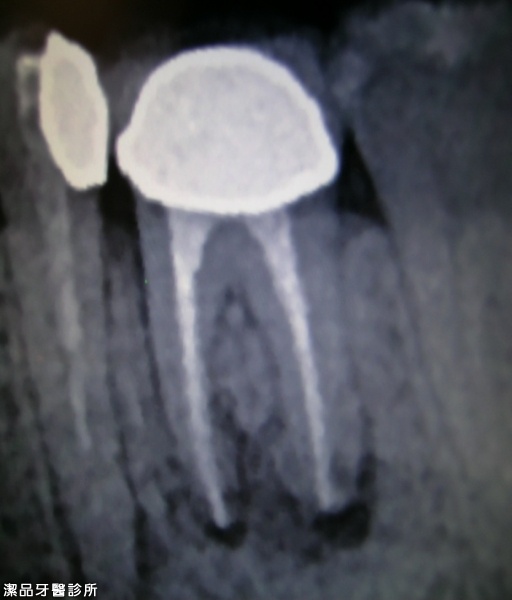

根管重新治療案例-002

案例簡述:

根管重新治療

兩年後 精準的根管治療後不再發炎,齒槽骨長回來了!